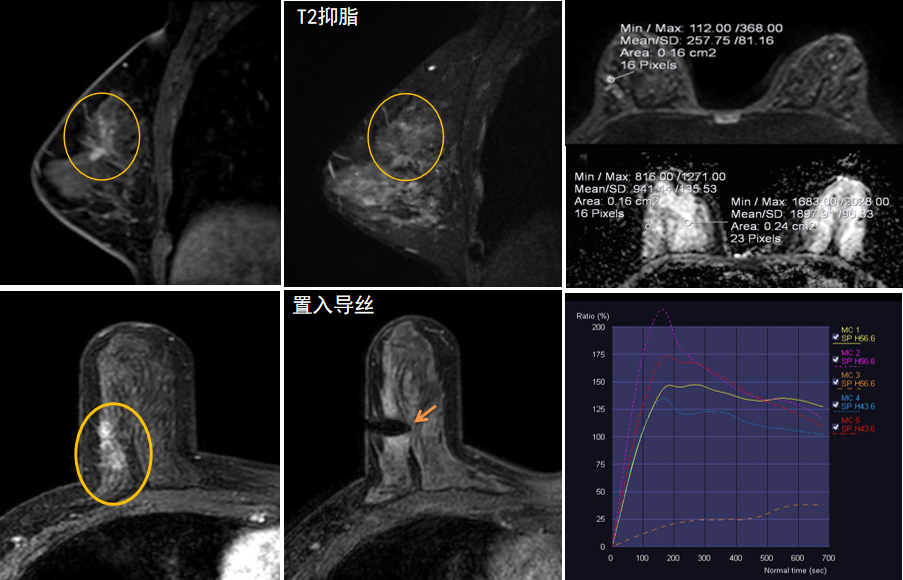

今年45歲的某女士,兩個(gè)月前行超聲檢查發(fā)現(xiàn)右乳結(jié)節(jié),乳腺X線(xiàn)攝影檢查提示右乳外上象限局部腺體結(jié)構(gòu)扭曲并簇狀無(wú)定形鈣化,為了進(jìn)一步評(píng)估病變性質(zhì)并確定范圍進(jìn)行了乳腺M(fèi)R平掃 DWI 增強(qiáng)的檢查,經(jīng)MR評(píng)估發(fā)現(xiàn)右乳病變范圍較廣,評(píng)估為BI-RADS 4類(lèi)可疑病變,需要取得病理學(xué)結(jié)果。

只能借助影像學(xué)引導(dǎo),但超聲僅顯示了病變中的小結(jié)節(jié),X線(xiàn)攝影(鉬靶)顯示的病變邊界比較模糊,要想做到精準(zhǔn)完整切除必須借助MR的引導(dǎo),而這一技術(shù)對(duì)軟硬件平臺(tái)及人員技術(shù)都有很高的要求,因此,多年來(lái)一直是我國(guó)乳腺病變?cè)\療的盲區(qū),經(jīng)常是MR發(fā)現(xiàn)可疑病變但卻無(wú)法處理。目前全國(guó)僅有少數(shù)幾家醫(yī)院開(kāi)展了這方面的部分工作。

陳寶瑩主任及其帶領(lǐng)的MR介入診療小組詳細(xì)詢(xún)問(wèn)了病情,分析了患者資料,并與患者和臨床醫(yī)生進(jìn)行了充分溝通,確定于手術(shù)前為患者實(shí)施MR引導(dǎo)下的病變穿刺導(dǎo)絲定位和體表范圍確定。手術(shù)前陳寶瑩主任帶領(lǐng)聶品醫(yī)師、馬小偉技師、韓愛(ài)萍護(hù)士長(zhǎng)等MR介入診療小組成員,借助MR高清的圖像顯示和定位系統(tǒng),確定病變范圍,精準(zhǔn)穿刺置入定位導(dǎo)絲,并準(zhǔn)確標(biāo)記出病變體表范圍,整個(gè)過(guò)程患者無(wú)任何不適。在定位導(dǎo)絲和體表范圍標(biāo)記的輔助下,甲乳外科劉曉敏主任精準(zhǔn)切除了病變,解除了患者的后顧之憂(yōu)。

國(guó)內(nèi)外指南均建議40歲以上的女性每年行一次雙乳X線(xiàn)攝影(鉬靶)檢查,以篩查乳腺癌。對(duì)于乳腺癌高危人群40歲以前即建議開(kāi)始乳腺癌篩查,除了進(jìn)行乳腺X線(xiàn)攝影(鉬靶)篩查外需要補(bǔ)充MR檢查,MR檢查敏感性最高,能夠發(fā)現(xiàn)大量X線(xiàn)攝影和超聲檢查陰性的可疑病變,基于多模態(tài)、多參數(shù)的結(jié)構(gòu)和功能成像的基礎(chǔ)上,MR能夠精準(zhǔn)顯示病變位置、范圍以及病變內(nèi)的活性區(qū)域,MR引導(dǎo)下的介入診療不但解決了僅在MR顯示的病變的處置難題,而且能夠精準(zhǔn)定位活性區(qū)域,保證了定位、活檢及旋切的準(zhǔn)確性。